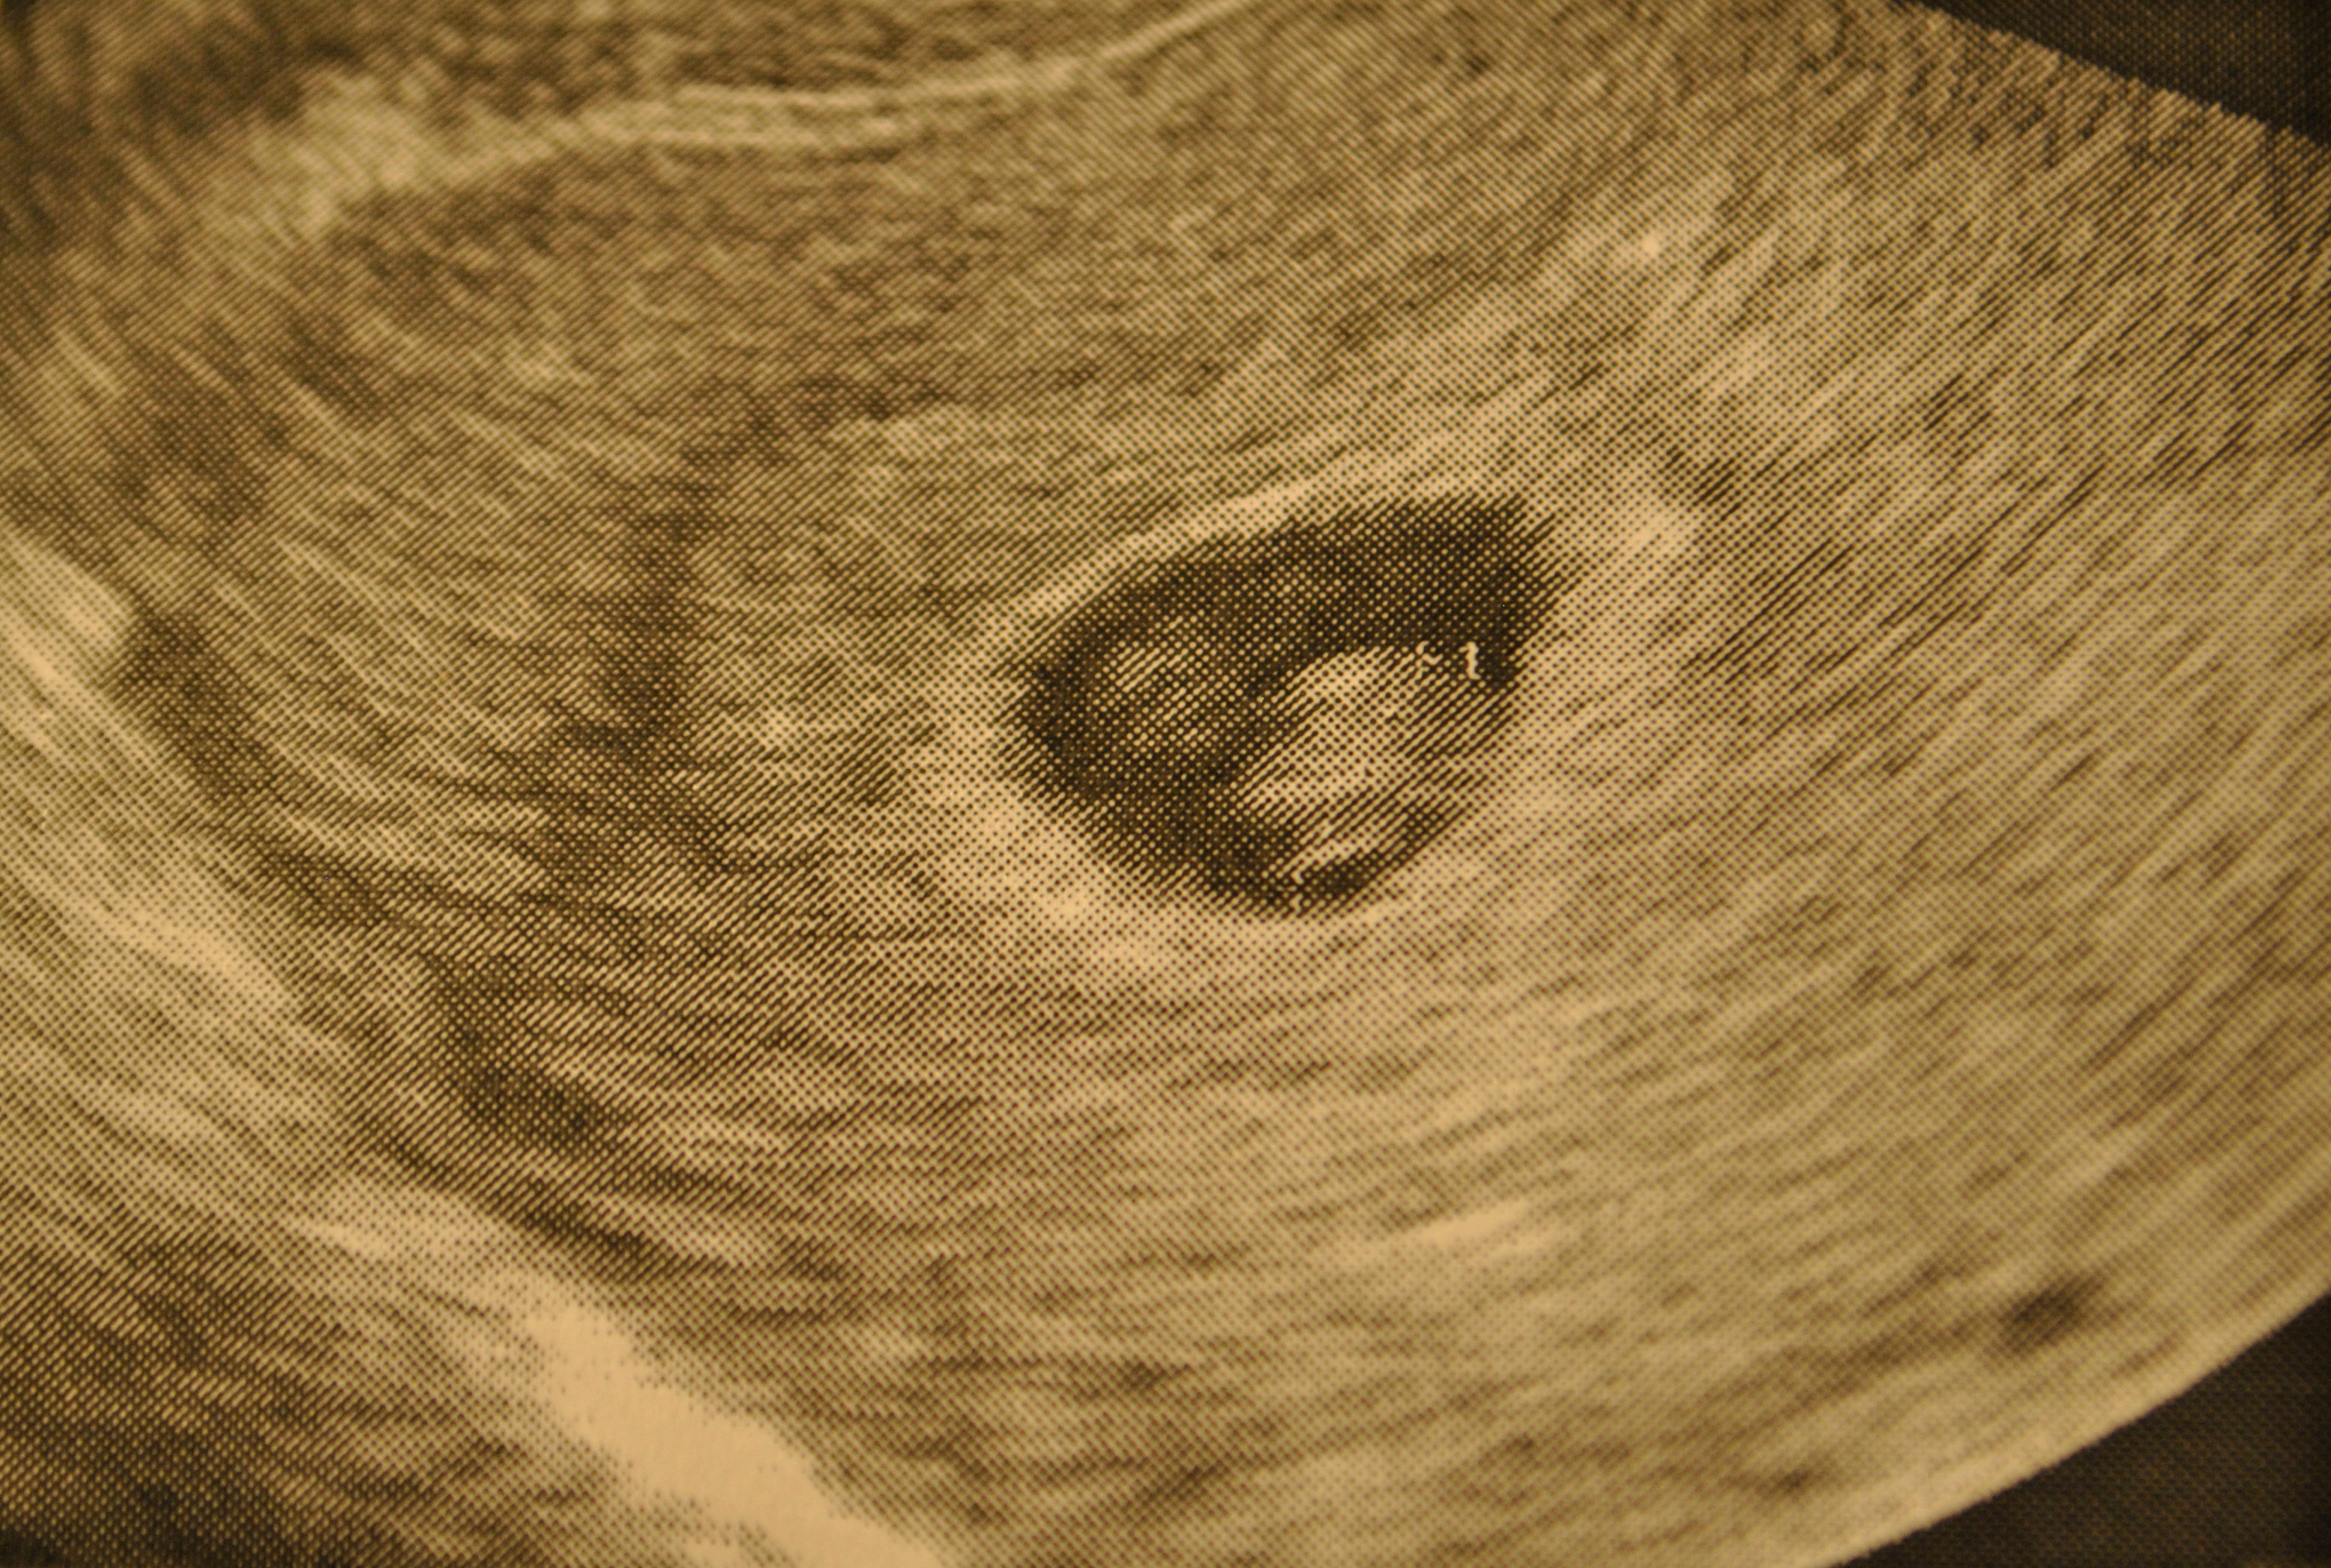

Вот она,наша малышка (не знаю почему,но на 95% уверенна что у нас дочка) в свои 5 неделек

КТР 8.9мм